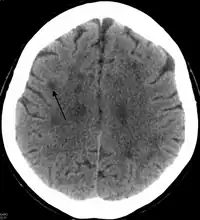

In HDLS, there is enlargement of the lateral ventricles and marked thinning or weakening of cerebral white matter.[6] The loss of white matter is caused by myelin loss. These changes are associated with diffuse gliosis, moderate loss of axons and many axonal spheroids.[1]

Standard MRI scans have been performed on 1.5 Tesla scanners with 5 mm thickness and 5 mm spacing to screen for white matter lesions in identified families. If signal intensities of the MRI scans are higher in white matter regions than in grey matter regions, the patient is considered to be at risk for HDLS, although a number of other disorders can also produce white matter changes and the findings are not diagnostic without genetic testing or pathologic confirmation.[2]

Tissue sections from brain biopsies or autopsy brains are commonly embedded in paraffin from which sections are cut an mounted on glass slides for histologic studies. Special stains for myelin and axonal pathology show the abnormal changes that are characteristic of HDLS are identified in white matter of the neocortex, basal ganglia, thalamus, midbrain, pons and spinal cord.[2][10] In addition to routine histologic methods (H&E staining), samples are evaluated with immunohistochemistry for ubiquitin, amyloid precursor protein, and neurofilament to characterize axonal changes and myelin basic protein for myelin pathology. Immunohistochemical stains for microglia (CD68 or HLA-DR) and astrocytes (GFAP) are also helpful techniques to characterize white matter pathology.[6] With a similar pathology to POLD, HDLS is commonly grouped as adult-onset leukoencephalopathy with axonal spheroids and pigmented glia (ALSP) so as to give these individually under-recognized conditions heightened attention.[3]